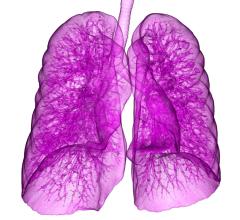

March 19, 2015 — Use of computed tomography coronary angiography (CTA), which provides 3-D images of the heart, coupled…

March 16, 2015 — Results from the PROMISE clinical trial confirmed what many cardiologists and radiologists have long…